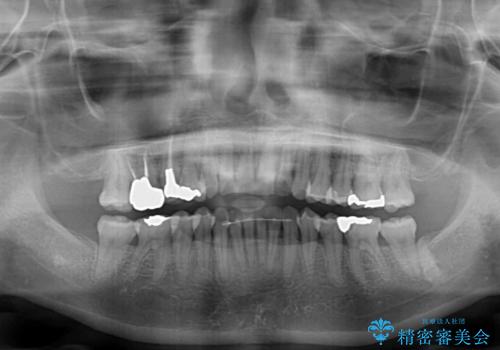

治療途中に前歯に歯髄充血を思わせる痛みが認められたため、無理のない歯の移動と頻繁な経過観察を行いました。

切端咬合はスムーズに解消され、前歯の負担を軽減させることができました。